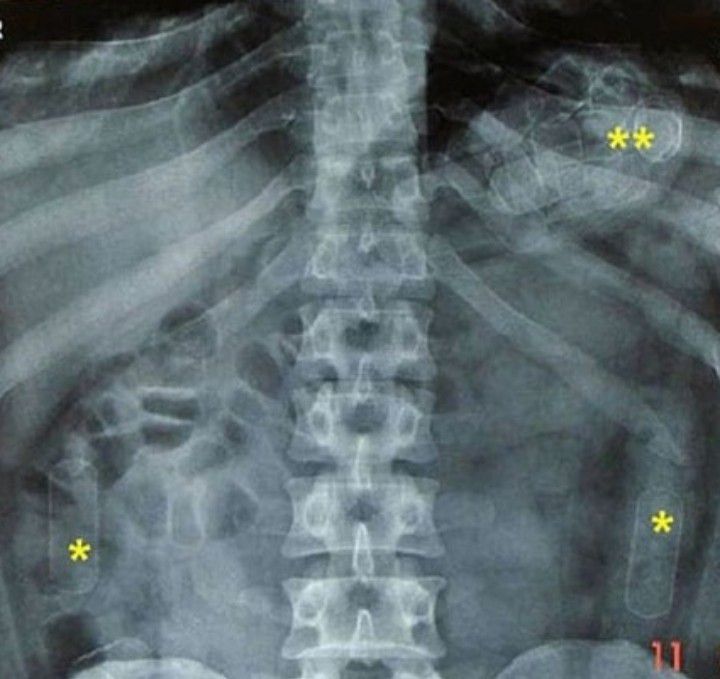

Foreign bodies

Foreign bodies on the radiograph coukr be seen clearly. What do you think this is?